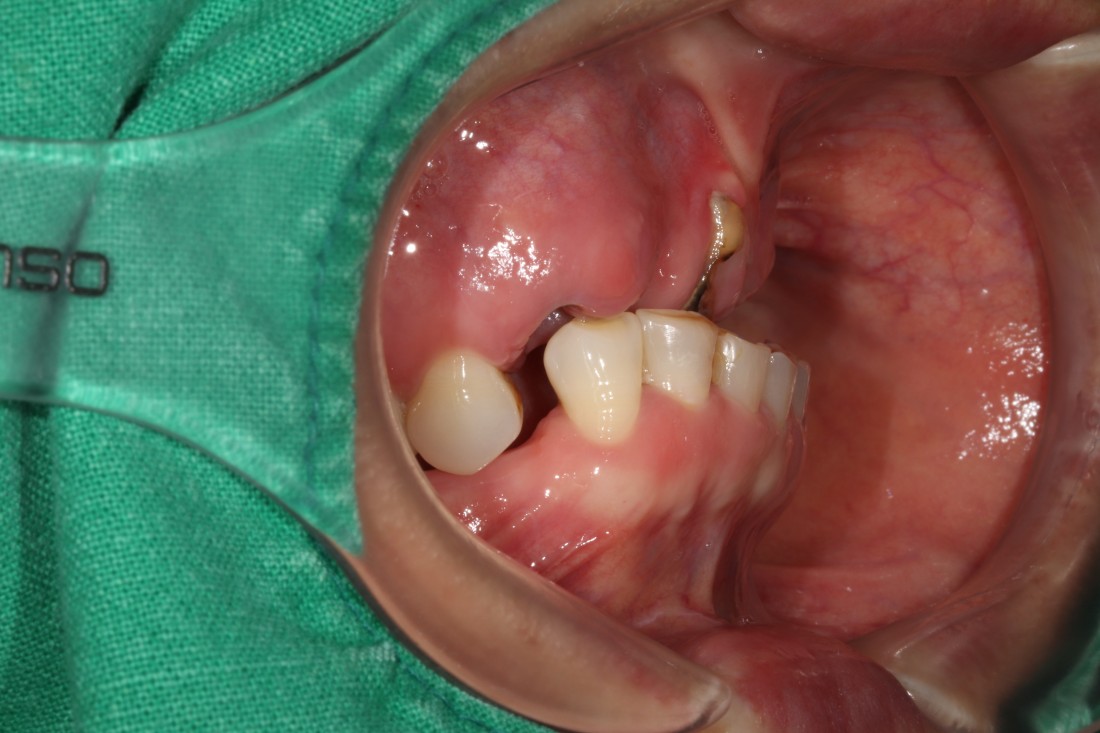

광주 상악임플란트 치과는

전체 임플란트 수술도

단 2번의 수술만으로

완성합니다.

광주 상악임플란트 치과에서는

위 / 아래 전체 임플란트를

붓기, 출혈, 통증을 최소화할 수 있는

디지털 가이드 임플란트 수술방법으로

단 2번의 수술만으로 완성하고 있습니다.